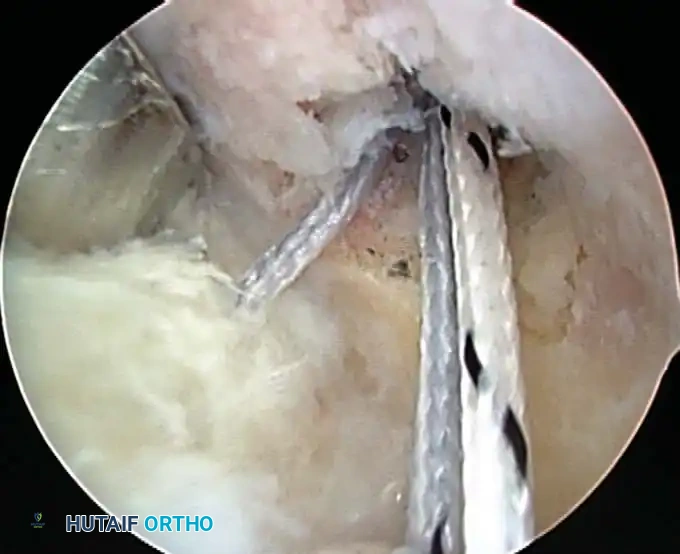

Once diagnostic evaluation is complete and hemostasis is secured, the therapeutic phase commences. Whether performing a SLAP repair, a Bankart stabilization, or a rotator cuff repair, the principles of tissue mobilization, anatomical footprint restoration, and secure biomechanical fixation remain paramount.

Modern arthroscopy relies heavily on suture anchors (biocomposite or all-suture constructs) and advanced arthroscopic knot-tying or knotless techniques. The ability to pass sutures through retracted, fibrotic tissue and secure them under appropriate tension without strangulating the microvascular supply is the hallmark of a master arthroscopist.